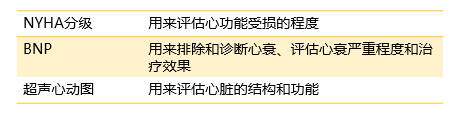

你知道病历和化验单上的结果都有哪些含义吗?

♥NYHA分级(纽约心功能分级):用来评价心功能受损的程度。按照诱发心衰的活动程度把心功能的受损状况分为四个等级,I级最轻,IV级最严重。NYHA分级帮助心衰患者和医生简易地了解心功能受损和病情严重程度,可以帮助选择合适的检查、治疗方案。

♥BNP(脑钠肽): 用来诊断心衰、评估心衰严重程度和治疗效果的生物标志物。反映的是左右心室、心脏瓣膜的功能。血浆BNP>80ng/L,诊断无症状心衰敏感性高,有利于心衰早期诊断,早期治疗。BNP也可以评估慢性心衰的严重程度和预后,BNP值越高,心衰的预后越差。另外,BNP可以辅助评价心衰治疗效果,降低病死率和住院风险。

如果是怀疑心衰的患者,检查显示BNP≥35pg/ml(或NT-proBNP≥125pg/ml),应及时检查超声心动图,排除心衰的可能。

♥超声心动图:用来评估心脏的结构、功能状况。心超可以准确地反应心脏结构、搏动和血液流动的情况。您可以关注心超最主要的指标:LVEF(左心室射血分数),如果LVEF低于50%,一般视为心功能不全。